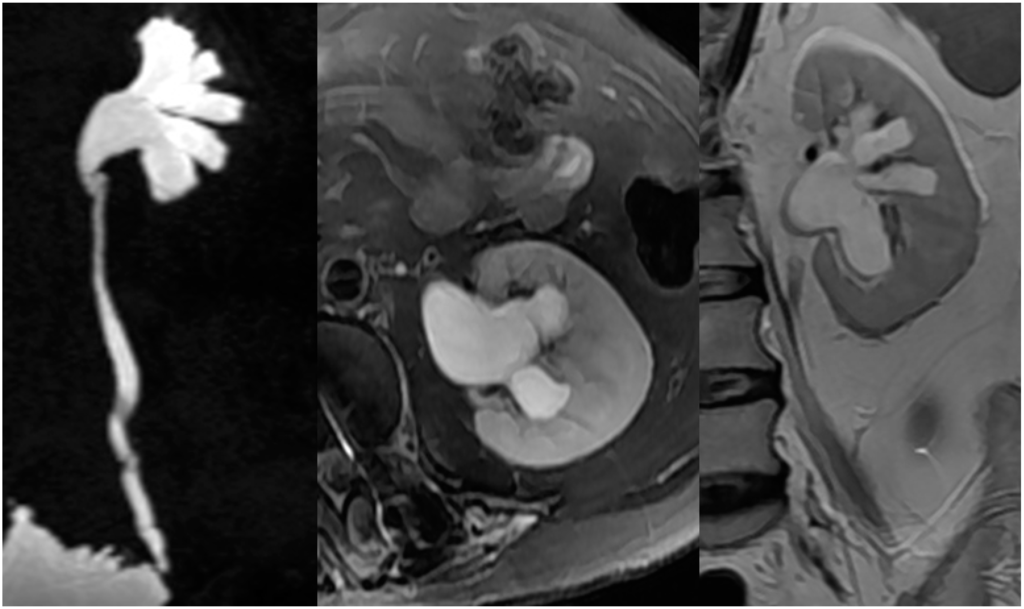

2.4. Upper Urinary Tract Imaging

2.4.1. Upper Urinary Tract Dilation (UUTD)

- Liao, L.M.; Zhang, F.; Chen, G. New grading system for upper urinary tract dilation using magnetic resonance urography in patients with neurogenic bladder. BMC Urol. 2014, 14, 38–45. [Google Scholar] [CrossRef] [PubMed]